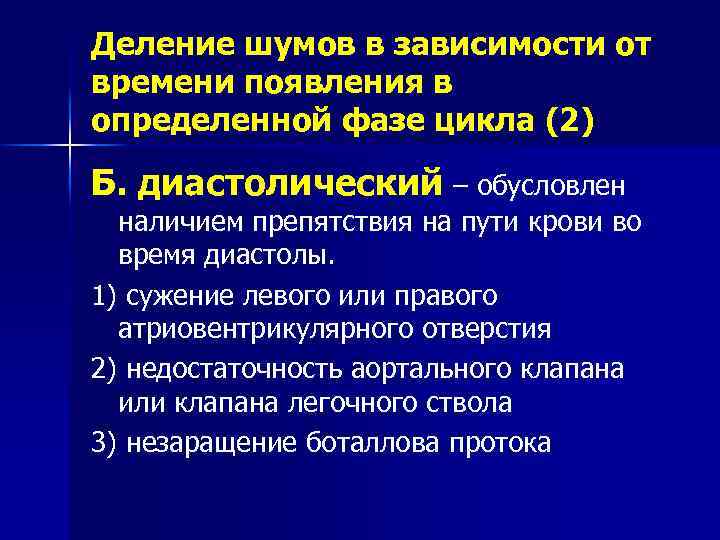

Деление шумов в зависимости от времени появления в определенной фазе цикла (2) Б. диастолический – обусловлен наличием препятствия на пути крови во время диастолы. 1) сужение левого или правого атриовентрикулярного отверстия 2) недостаточность аортального клапана или клапана легочного ствола 3) незаращение боталлова протока